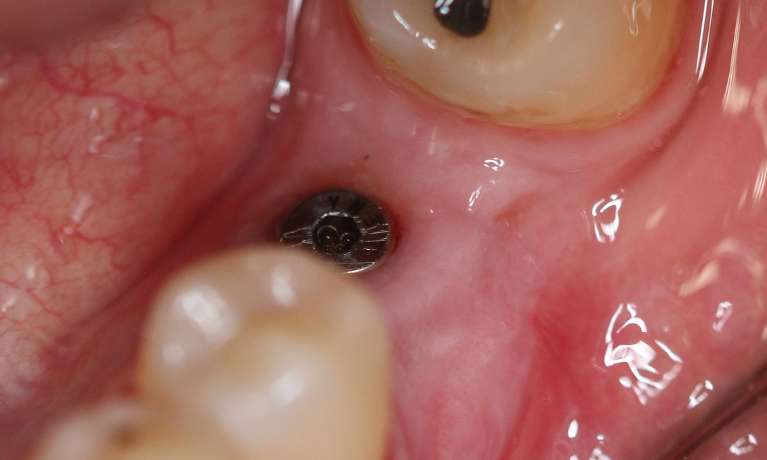

This patient experienced trauma to a single tooth, rendering it irreparable and necessitating its removal. Our solution involved replacing the compromised tooth with a dental implant, providing a strong, natural-looking, and permanent restoration.